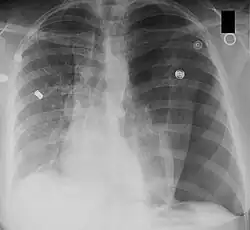

Left-sided tension pneumothorax. Note the area without lung markings which is air in the pleural space. Also note the tracheal and mediastinal shift from the patient's left to right.

Tension pneumothorax

A pneumothorax occurs when air collects in the pleural space around the lungs. Normally, this space has negative pressure to allow the lung to fill. Pressure increases as more air enters this space.[7] The lung collapses, impairing normal breathing. Surrounding structures may also shift. When severe enough to cause these shifts and hypotension, it is called a tension pneumothorax. This is life-threatening. The increased pressure inside the chest can compress the heart and lead to a collapse of the blood vessels that drain to the heart. The veins supplying the heart are compressed, in turn decreasing venous return.[7] With the heart unable to fill, cardiac output drops. Hypotension and shock ensue. If not rapidly treated, it can lead to cardiac arrest and death.[8]

A chest X-ray can rapidly identify a pneumothorax, seen as absence of lung markings. Ultrasound can show the lack of lung sliding. However, imaging should not delay treatment.[8] CT angiography is the standard of diagnosis of pulmonary embolism. Clots appear in the vasculature as filling defects.[18]